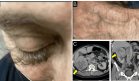

Esto motivó su traslado a un centro terciario, donde se evidenció una úlcera por presión grado IV de aproximadamente 20 cm de diámetro, acompañada de signos sistémicos de infección, como fiebre, leucocitosis y elevación marcada de reactantes de fase aguda.

Desde el punto de vista quirúrgico, se realizó un desbridamiento extenso de tejido necrótico, seguido de terapia de presión negativa y, finalmente, reconstrucción con colgajo glúteo V-Y, que logró una cobertura estable sin complicaciones postoperatorias.

La resonancia magnética mostró hiperintensidad en T2 a nivel del foramen ciático mayor, compatible con afectación inflamatoria o por compresión secundaria a la ulceración profunda.